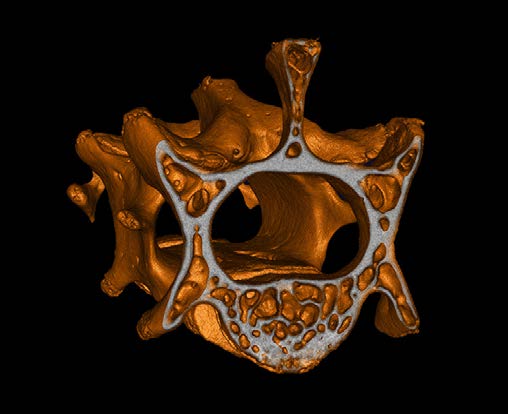

CosmoScan GX IIIは特に高い空間分解能を持ち、5µmまでの解像度と2.9µmのピクセルサイズ(FOV:8mm)を誇ります。これにより小さい骨の細かな解剖学的構造を含むex vivoサンプルの高品質な画像が得られます。

- 空間分解能 = 5µm 最小ピクセルサイズ = 2.9µm